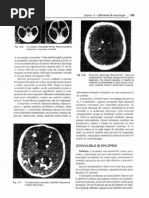

Fractura atipică a stâncii temporalului

Fractura oblică a stâncii temporalului